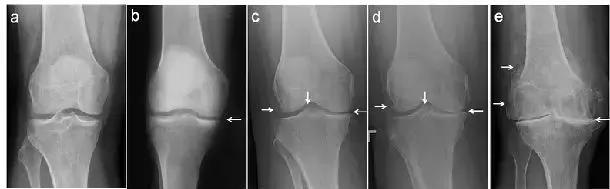

经常会遇到有人发现自己“关节疼、肿”,到医院拍片,诊断为“滑膜炎”(图1 a,b)、“骨质增生”(图1 c,d,e),还有诊断为“关节炎”的(图1 d,e)。那到底是那种病?我们对这几种病名分别了解一下。

图1. 膝关节的各种X线拍片表现

从上可见,早期的(骨)关节炎就是滑膜炎。因为在常规X线片上无法观察到明显的关节周围骨质增生(即骨赘形成),或关节间隙变窄(图1c,1d,1e),因此被称之为“滑膜炎”。

患者关节肿痛,拍片子后看到报告单上描述的“骨质增生”,同时观察到X线片上关节(股骨或胫骨)周缘或髁间棘处增生的骨质(图1c,1d,1e左侧和中间白箭头),就断定自己得了“骨质增生”(有了“骨刺”)。其实,“骨质增生”只是对关节内骨赘形成这一病变形态的描述,根本就不是一个诊断。因为这一描述无法确切的说明发病原因,因而进一步的治疗也就无从下手。打个比方,就像说某人“个子高了”,我们并没有办法知道这个人的个子高到什么程度了,也无法知道她(他)的个子为什么高了。既然无法确切的诊断关节肿痛的原因,治疗也就无从谈起。

从前面我们可以知道,过度活动或年龄增大会造成关节磨损。轻度的关节损伤会造成“滑膜炎”;重度的关节损伤或年龄增大造成关节磨损会导致“退行性骨关节炎”,也就是常说的“关节炎”(图1c,1d,1e)。

- 对于晚上疼痛,难以入睡;以及因为关节疼痛无法出门,生活质量极差的骨关节炎患者(图1e)可以考虑关节置换。